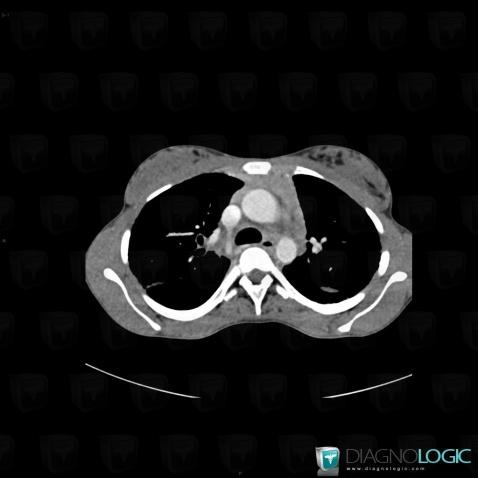

Sarcoïdose, Médiastin, Scanner

Voici les informations spécifiques à l'image clé ci dessus:

- Diagnostic Sarcoïdose, Localisation(s) Médiastin, comportant les gammes Masse médiastinale supérieure